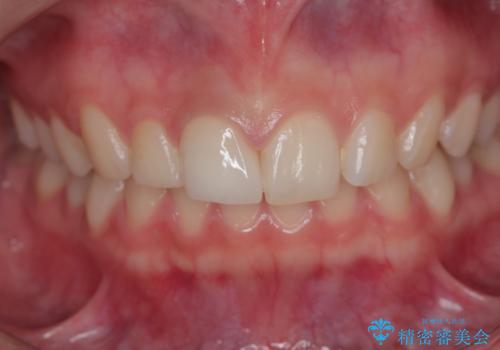

適合の良い被せ物が入り、患者様に満足していただけました。